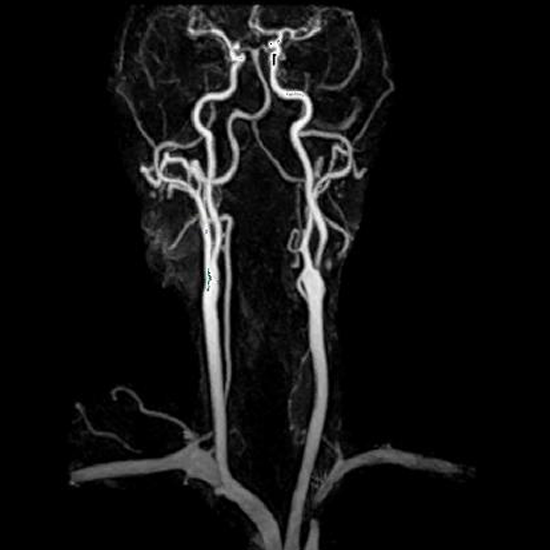

Magnetic Resonance (MR) Angiography is used to make images of soft tissues, bones, and interior bodily components. There is no use of radiation, but contrast dye may be injected during the examination. Despite this, MRA is still capable of producing high-quality images without the use of contrast agents. Consequently, it is advantageous for people with allergies or damaged kidney or liver function.

Angiograms are used to identify and treat blood vessel diseases. It is typically used to detect if the neck arteries are constricted or blocked. The neck is scanned using MRA to provide 3D pictures of the blood vessels.